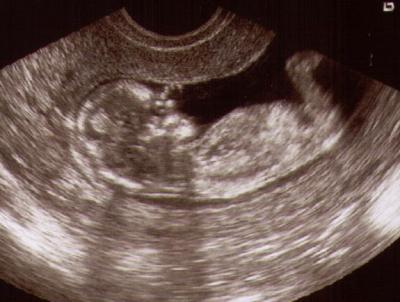

Hallo Mädels, soooooooooo ich bin auch wieder da und das Baby ist soooooo derb gewachsen in den letzten 4 Wochen wahnsinn... NFM war bei 1.1 und somit alles schick. UUND heute waren die Kinder mit zu US weil der Doc meinte das sie jetzt mitkommen sollten wenn das Baby noch ganz auf den Monitor passt ;-) Die beiden waren total begeistert und konnten sich gar nicht satt sehen am Baby. Haben Hände und Füße erkannt und durften das Herz hören und sehen. Natürlich wurde der Doc mit Fragen gelöchert -die allerbeste Aussage war das es jetzt ja gar keine Bohne oder Erdnuss mehr ist *lach Mein Baby schauen fiel dann ein wenig kürzer aus ABER das war okay weil die beiden sooooo glücklich waren - dafür gabs für Mama nen Bild ;-) Er war auch sonst ganz zufrieden mit mir - ausser das der Eisenwert höher sein könnte (7,3 zur Zeit) und das ich im Nov nen kontrollbedürftigen Krebsabstrich hatte (aber er sagt das ist nichts worüber man sich nen Kopf machen muss - lieg bei der Einstufung bei Grad II) - also haben wir die Kontrolle auvh gleich gemacht. Am besten war das er meinte man sieht mir an das es mir so viel besser geht und das ihn das freut. Ach ja was mein plötzlich wachenden Bauch angeht so ist das auch alles normal und es ist ja auch schön wenn man einen hat. Laut Wage von ihm hab ich die letzten 4 Wochen 1,9kg zugenommen (mit Sachen gewogen) Hach und es ist einfach nur schön das alles gut ist. In 4 Wochen darf ich wieder kommen und Anfang Mai zur Feindiagnostik zum Spezialisten. LG Isa die noch auf Wolke 7 ist wegen Baby TV

Bild zu Zurück von VU + NFM -> die Kinder durften Baby schauen :-))) - Forum für September - Mamis

Hey Glückwunsch das alles so gut gelaufen ist. Das Bild ist totalllllll süß Freue mich für dich, weiterhin alles Gute Liebe Grüße